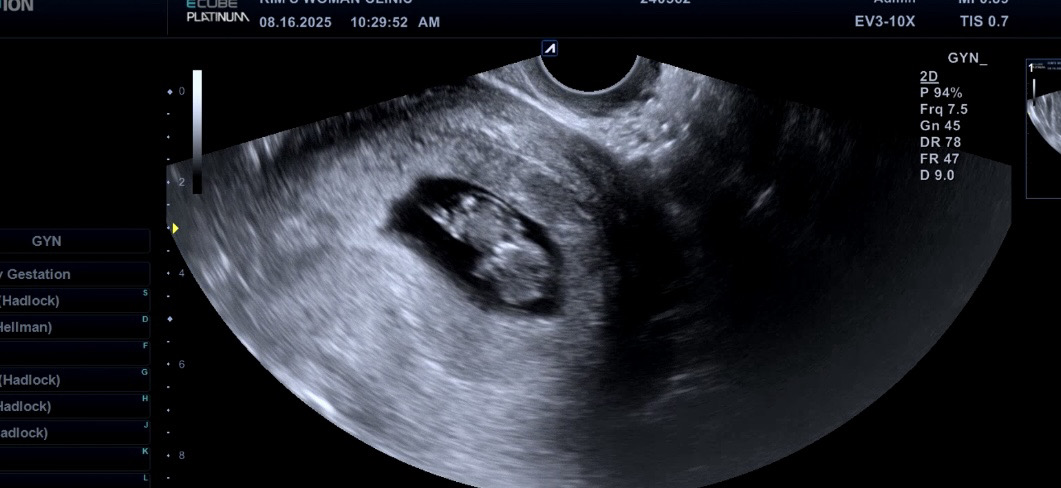

10주차 진입!!

7주차에 피고임으로 고생했지만 10주차 진입인 오늘 다녀오니 어느정도 안심해도 된다고 하셨어요!! 심장소리도 좋고 꿈틀거리는거도 보고 왔습니다! 무럭무럭 잘자라주고 있어서 너무 행복합니당😁 다들 출산일까지 화이팅 해봐요🫶🏻